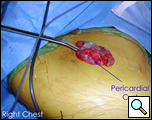

In the operating room, under general anesthesia and one lung ventilation, the thoracoscope was introduced at the right midaxillary line and the 7th intercostal space (Video 1 below). The cyst was readily visualized at the anterolateral aspect of the right pericardium, measuring approximately 9x6cm (Figure 3). The phrenic nerve was seen posterior to the cyst. The second incision was made at the anterior axillary line in the 4th intercostal space. A ring clamp was used to grasp the cyst (Figure 4). The third incision was made at the scapula line in the 5th intercostal space. Thoracoscopic scissors and cautery (at a low setting to minimize the chance of cardiac arrhythmias) were used through that port to dissect the cyst from the pericardium (Figure 5). The connection between the cyst and the pericardial space was identified. It was small, and was divided with the scissors. The dissection of the posterior aspect of the cyst completed the removal. The phrenic nerve was clearly visualized at all times. The pathology report confirmed the diagnosis of a benign mesothelial-lined cyst (Figure 6).

| Figure 5. Resection of cyst with view of phrenic nerve. | Figure 6. Resected specimen |